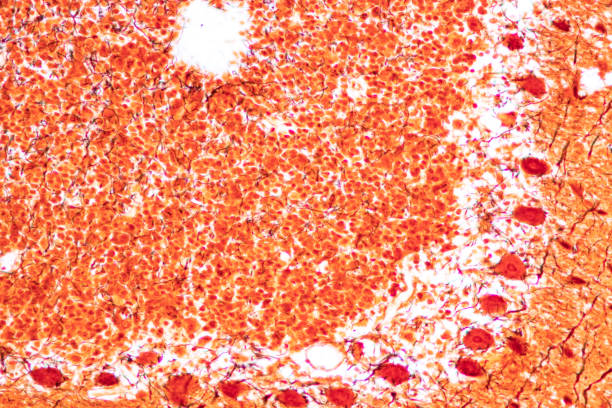

또한, 높은 요산수치는 통풍과 관련된 질환이 발생할 수도 있습니다. 요산 결정이 혈액 내에 쌓이고 관절에 침착되면, 통풍을 유발하게 됩니다. 통풍은 관절에 염증을 일으켜 통증과 염증성 관절염을 야기할 수 있습니다.

높은 요산수치는 또한 심혈관 질환의 발생 위험성을 증가시킵니다. 요산 결정은 혈관 벽에 침착되어 혈액 순환을 어렵게 하고, 혈액 내의 콜레스테롤 수치를 증가시킬 수 있습니다. 이로 인해 고혈압, 협심증, 심근경색 등의 심혈관질환의 발생 위험이 증가할 수 있습니다.